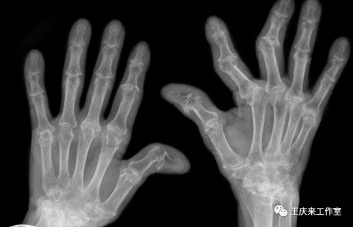

04辅助检查

类风湿关节炎患者类风湿因子阳性率达75%,骨关节炎患者的类风湿因子呈阴性。

另外抗环瓜氨酸抗体检测也有助于类风湿性关节炎的诊断。也可以根据关节B超、放射线检查等对诊断做出帮助。

另外类风湿性关节炎造成的关节变形,具有独特之处,如:手指天鹅颈样、钮扣花样畸形。而骨性关节炎则没有这种典型的表现。